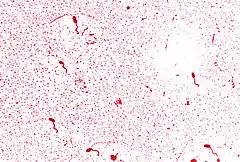

Холерний вібріон (Vibrio cholerae) — грамнегативний мікроб, що спор і капсул не утворює, має форму зігнутої палички, що нагадує кому, завдяки наявності джгутика дуже рухливий. Його добре культивують на простих і лужних поживних середовищах — 1 % пептонна вода, МПБ, лужний агар. Росте на поживних середовищах при температурі +30-40°С, оптимальною є температура +37°С.